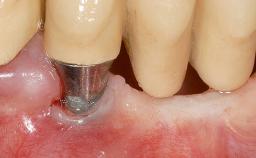

A 30-year-old woman was referred by her general dentist for evaluation of an esthetic complication related to previous implant treatment for congenitally missing maxillary lateral incisors. The patient’s chief complaint was the inadequate esthetic appearance of her smile. The case demonstrates the use of a combined approach to achieve optimal results. Two different flap designs - a tunnel technique and a coronally advanced flap - are employed based on the surgical objectives for the affected site.

Periodontal Plastic Surgery and Prosthetic Procedures to Treat Peri-Implant Soft-Tissue Dehiscences

Type of Implants Two-Piece

Attachment Two-Piece

Abutment Type Standard